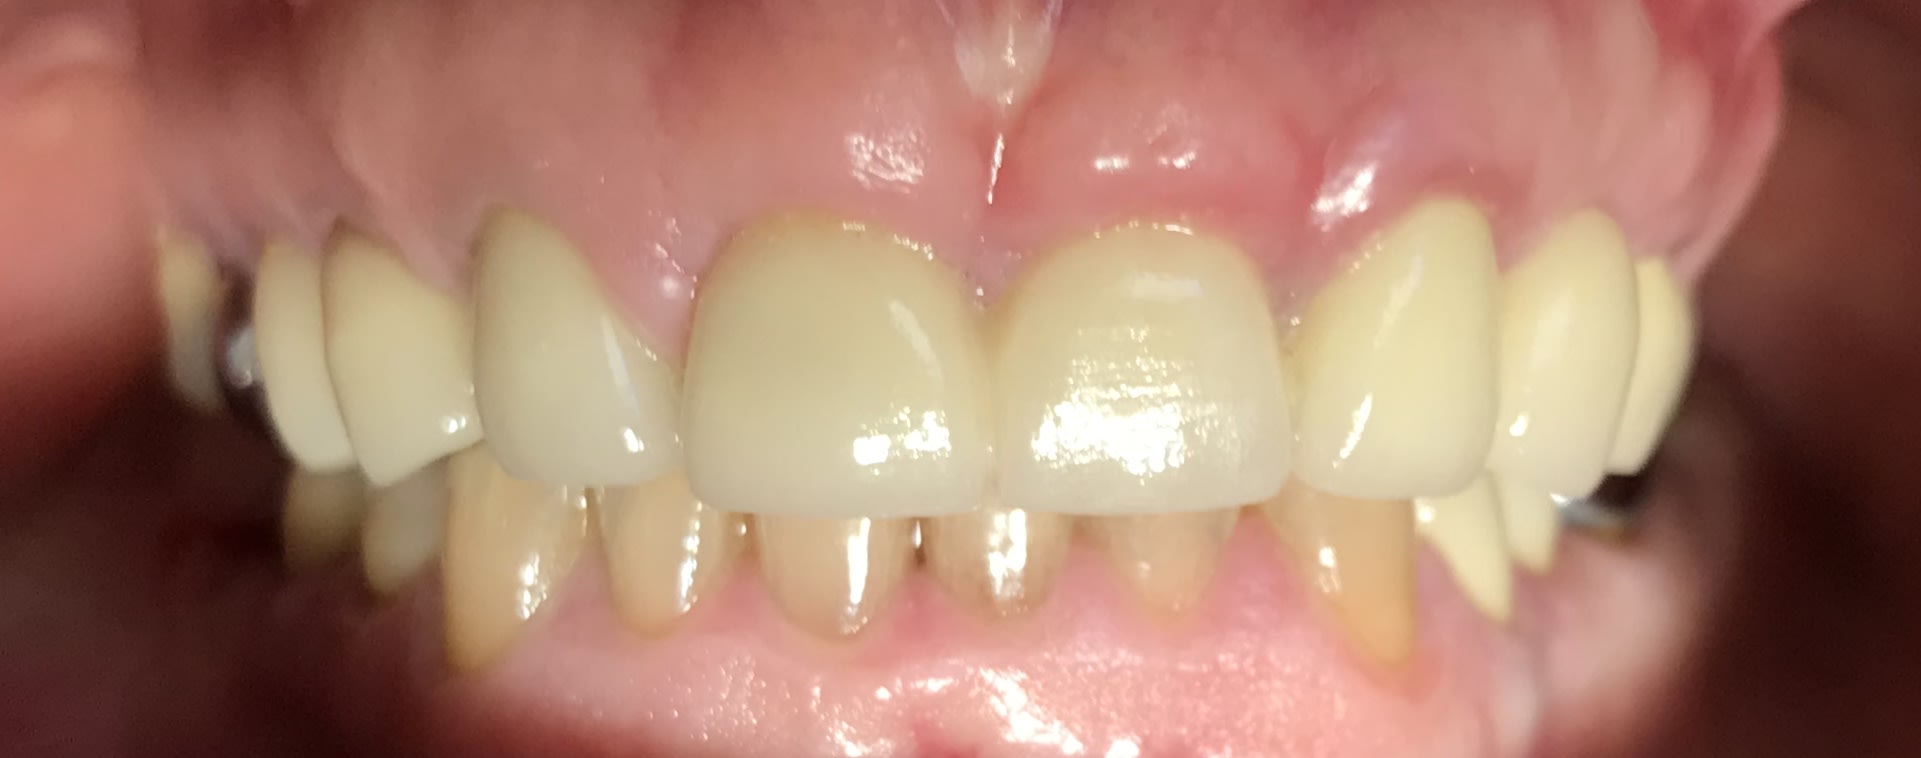

En attendant que le nouveau réponde ... Dans un style différent : 38 ans . très complexé. Aucun dentiste n’a voulu le toucher (pour le secteur antérieur) . Je lui ai dit qu’il fallait lui déglinguer la mâchoire. Sauf qu’il ne veut pas faire de chirurgie orthognatique, c’est sa seule condition . Par contre est prêt à mettre n’importe quel prix pour retrouver un beau sourire. N’est ni fermé à l’ortho , ni fermé à l’implantologie.

Ex des centrales et bridge 12-22, je pense que tu peux faire un truc sympa. Teste sur ton plâtre.

Mouais, mouais, mouais... Très complexé... Le problème, c'est que ça se limite pas qu'au dent...

Pour moi, ortho, orthopédie ou rien. J'aime bien rien.

à condition de maitriser l'hygiene avant tout et de preserver les canines à tout prix

et à condition que l'occlusion soit bien tolérée examen soigneux des ATM et des muscles masticateurs

la seule solution esthétique pour ne pas lui faire des contrales de lapin passe par une fausse gencive

Le cas du début c'est avant tout une supraclusie carabinée.